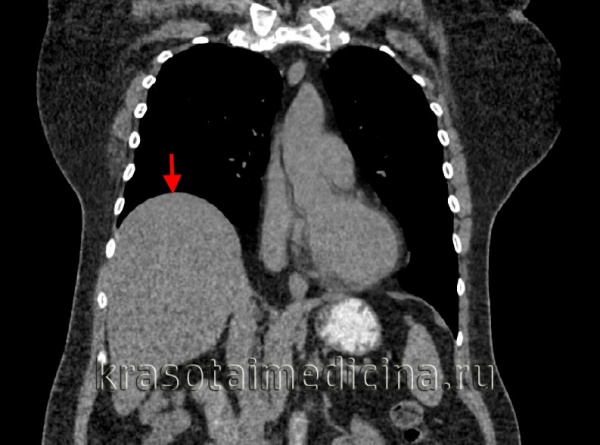

- Лучевая диагностика. Рентгенография и КТ грудной клетки являются наиболее информативными методами исследования диафрагмы. На рентгенограмме визуализируется высокое расположение одного из куполов (уровень II–V ребра). При рентгеноскопии обнаруживается парадоксальное движение диафрагмального свода. Использование контраста позволяет выявить перегибы пищевода, желудка, смещение органов пищеварения кверху. КТ наиболее точно определяет степень релаксации, помогает распознать вторичную патологию внутренних органов.